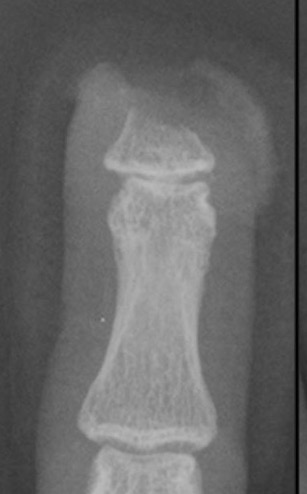

Detipping

Definition

Distal to insertion of flexor and extensor tendons

Tissue involved

Pulp only

Nail bed

Bone